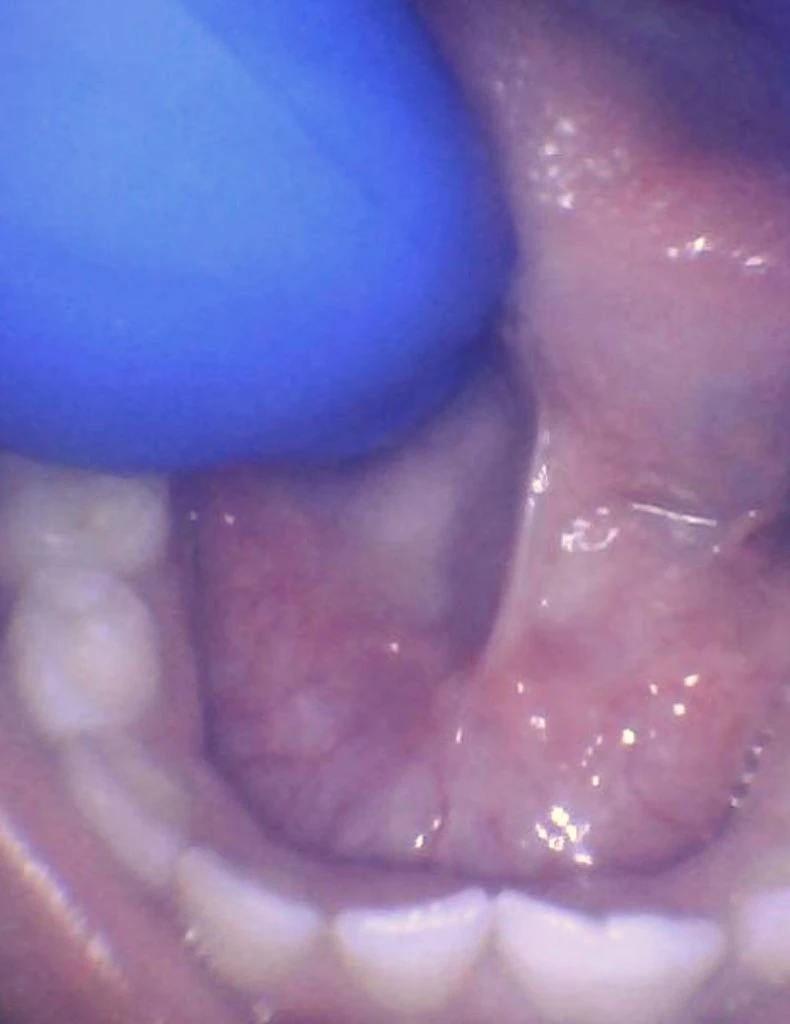

These images show the spectrum of lip restriction in an infant.

View lip restrictions

These images show the spectrum of lip restriction in a child.